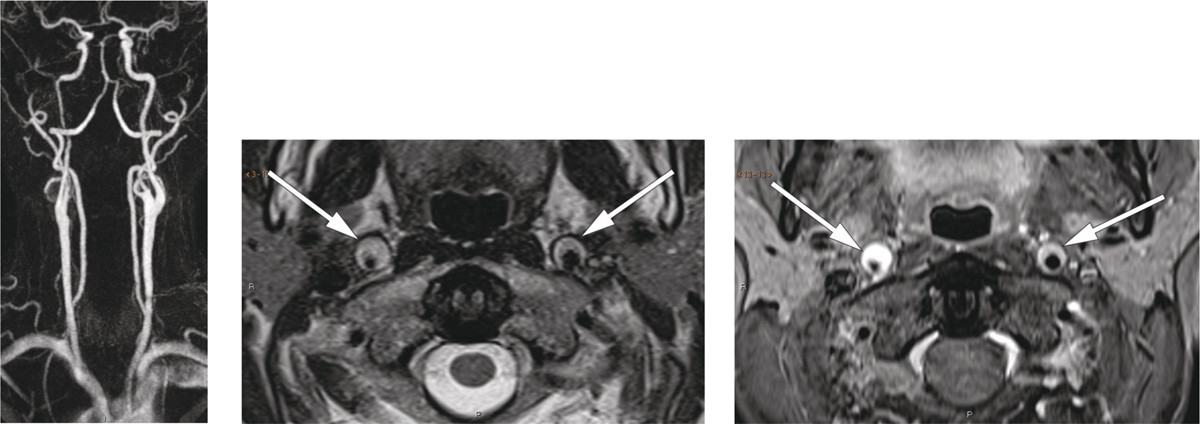

Nevrologisk undersøkelse avdekket Horners syndrom. CT-angiografi viste fortykket karvegg i begge a. carotis interna, mest uttalt på høyre side, fra like over bifurkaturen til skallebasis. MR-angiografi og T2-vektede bilder bekreftet bilateral carotisdisseksjon, med minste lumendiameter 2 mm på høyre side (bildet til venstre og bildet i midten). Fettsupprimerte T1-vektede bilder (bildet til høyre) viste høyt signal i arterieveggene, forenlig med intramurale hematomer.

Hosteattanfallene i kombinasjon med fysisk aktivitet ble vurdert som sannsynlig årsak til disseksjonen. Risikoen for hjerneinfarkt ble vurdert som høy, og pasienten ble behandlet med acetylsalicylsyre 75 mg og klopidogrel 75 mg i fire måneder, deretter monoterapi med acetylsalisylsyre i to måneder. Behandlingen ble avsluttet da MR-kontroll viste fullstendig normalisering av halskarene. Pasienten hadde fortsatt en lett anisokori, men var ellers symptomfri.